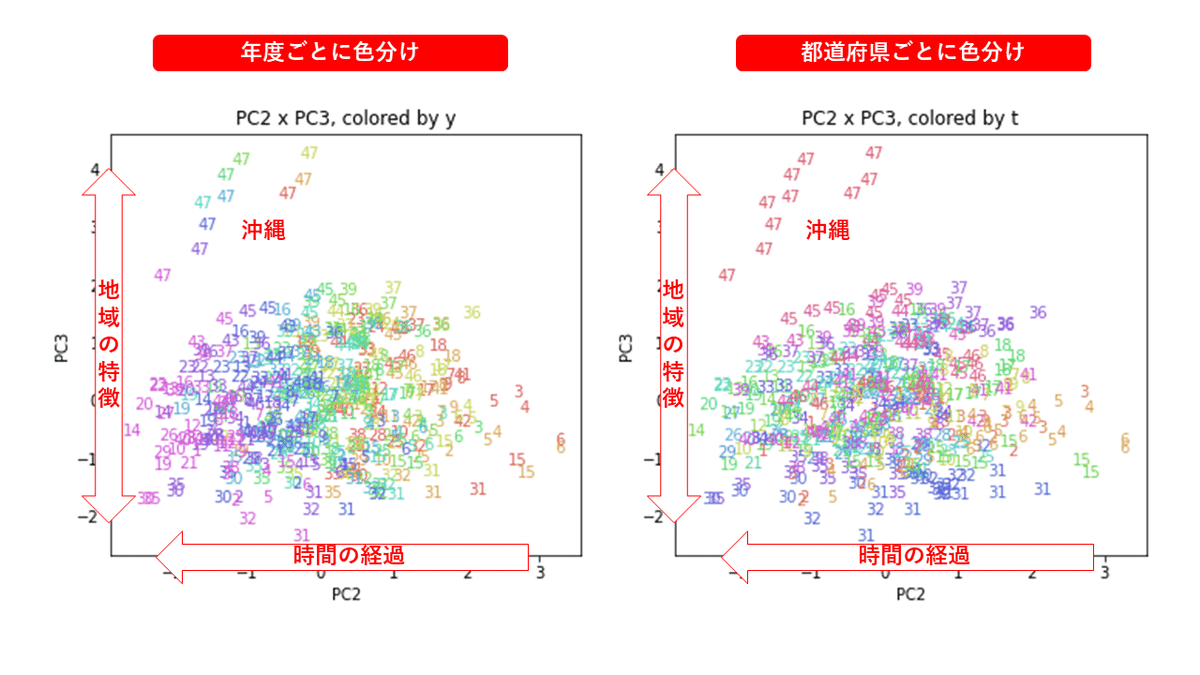

PCAの結果の第n主成分をPCnと表記します。

医療費データの場合と同様に、PCAの結果を見やすく表示するため、seabornのカラーパレットを使って、年月別、都道府県別に色分けして図示してみます(左側が年月別に色分け、右側が都道府県別に色分け)。PC1~PC8まで表示しました。

都道府県番号の表示

上の色分けだけでは都道府県が区別しにくいので、医療費データの場合と同様に、点の代わりに都道府県番号をプロットした図も描いておきます(色分けは上と同じ)。

医療費データの場合ほどはっきりとはしていませんが、PC2が概ね時間の経過を表す成分で、残りの成分が時点によって変わらない地域の特徴を表す成分となっているようです。

また、PC1×PC3を見ると、47沖縄が他の都道府県からかなり離れたところに位置しており、沖縄の地域差が際立っているのが分かります。これは、以前別の記事で年齢階級のない健診データでPCAを実行した場合と似た結果となっています。

今回は、医療費データと同様に、健診データ240次元についてPCAを実行してみました。PCAの結果、医療費データの場合ほどはっきりしとはしていませんが、第2主成分が概ね時間の経過を表す成分で、時間軸に沿った全体的な動き(全国的な動き)を表しており、それ以外の成分が地域の特徴を表す成分で、この10年間あまり変わっていないことがわかりました。